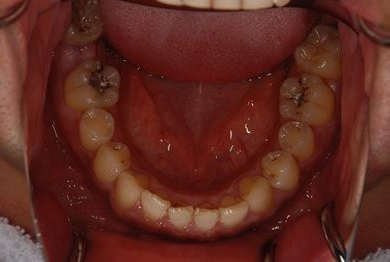

インプラントの症例写真 IMPLANT

抜歯即日スピードインプラント治療

| 性別/年齢 | 男性 / 36歳 | ||||||||||||||||||||||||||||||||

| 主訴 | 歯が折れているので、インプラントにしたい。 | ||||||||||||||||||||||||||||||||

| 治療方針 | 抜歯と同時にインプラント埋入を行い、治療期間を短縮する。 | ||||||||||||||||||||||||||||||||

| 治療内容 | インプラント2本(抜歯即日インプラント治療)、ジルコニアフレームオールセラミッククラウン1本、オールセラミッククラウン2本(セラミック用土台2本)、メタルボンドセラミッククラウン1本 | ||||||||||||||||||||||||||||||||